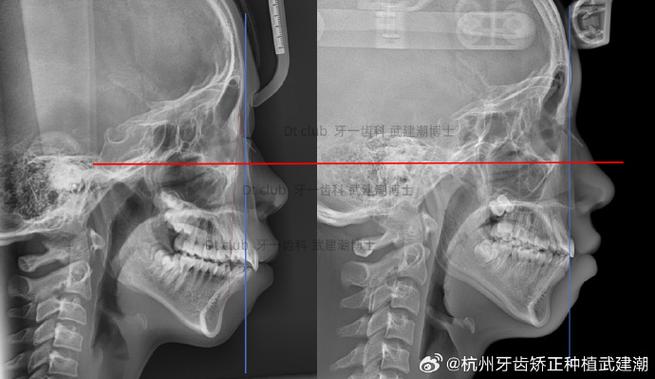

通过X线曲面断层片、CBCT等影像学检查,评估牙槽骨的height、宽度、密度及形态,明确是否存在骨缺损、吸收或形态异常,对存在牙周炎的患者,需先完成牙周基础治疗(洁治、刮治、根面平整),待牙槽骨稳定后再启动正畸治疗;对牙槽骨严重吸收者,需联合牙周手术(如骨移植、引导组织再生术)改善骨支持,为正畸治疗奠定基础。

A:正畸复发后,牙槽骨常表现为适应性改建:若牙齿向唇侧移位,唇侧牙槽骨可能因持续压力发生进一步吸收,舌侧牙槽骨则可能因张力刺激出现骨沉积,但整体骨量可能减少;若牙齿发生扭转或倾斜,牙槽骨骨小梁排列紊乱,受力区域骨密度降低,非受力区域出现废用性骨质疏松,影像学检查中,CBCT可清晰显示牙槽骨的height(牙槽嵴顶至根尖的距离)、width(牙根唇舌侧骨皮质厚度)、密度(灰度值)及骨小梁结构:若牙槽嵴height降低、唇舌侧骨宽度<2mm、骨密度较治疗前降低,提示牙槽骨吸收;若骨小梁排列稀疏、无规律,提示改建失衡。